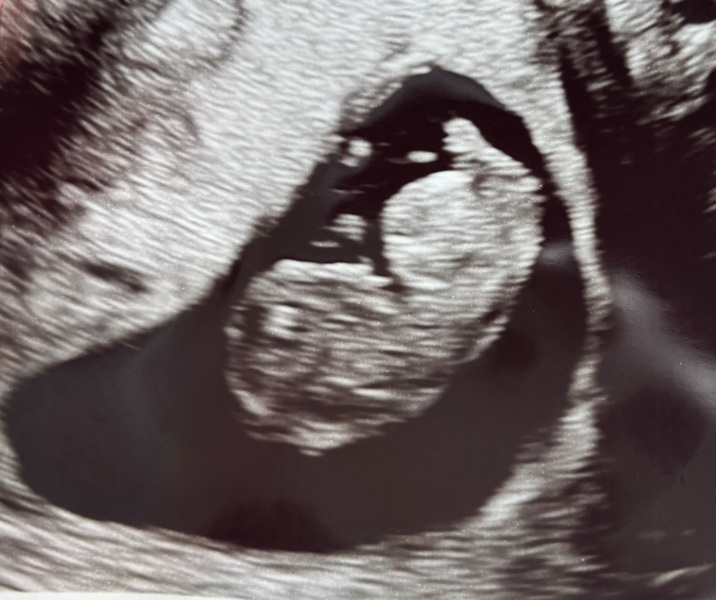

Here is my little one, all looking well, thank goodness. My due date has moved to September! I was stick to this thread though! I was hoping for a photo to guess the sex, but baby did not oblige!

@WickWood wow look at your baby! September now eh?! Xx aww

@WickWood that’s amazing! Bet it was so lovely to see your little one 🥰